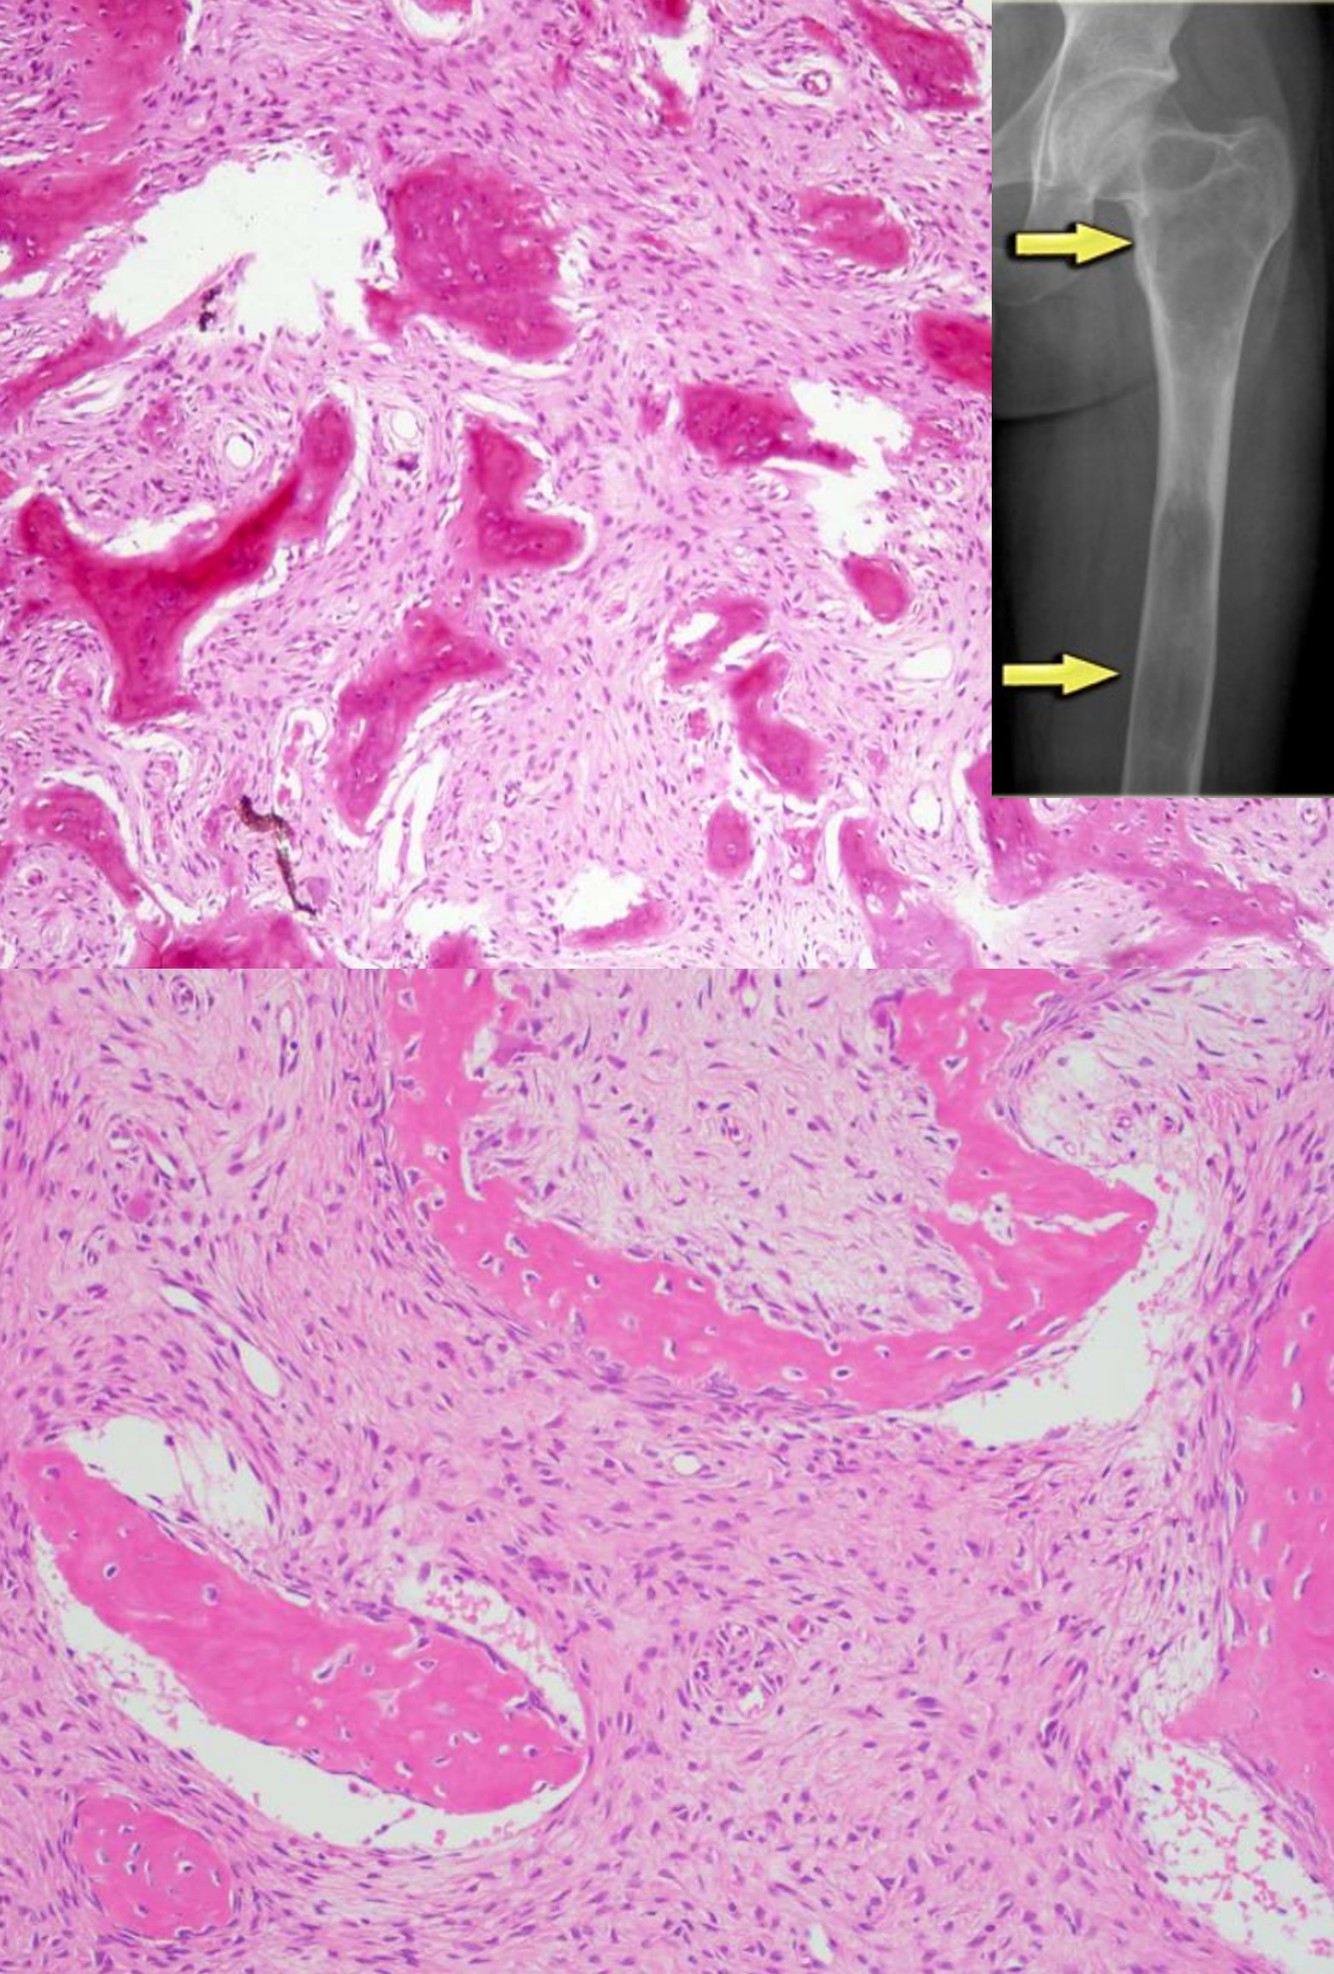

PAROSTEAL OSTEOSARCOMA

IDH2/IDH2 mutations

PERIOSTEAL OSTEOSARCOMA

100% have IDH2/IDH2 mutations

HIGH-GRADE SURFACE OSTEOSARCOMA